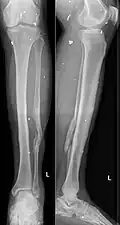

Grenade fragments in the soft tissue of the lower leg (along with an old fracture of the fibula)